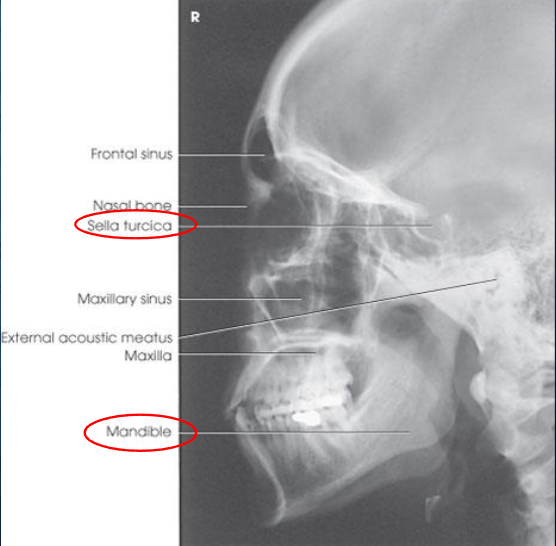

Lateral skull

Lateral skull image criteria

entire cranium without rotation or tilt

superimposed orbital roofs and greater wings of sphenoid

superimposed mastoid regions, EAMs, and TMJs

sella turcica in profile

penetration of parietal region

no overlap of c-spine by mandible